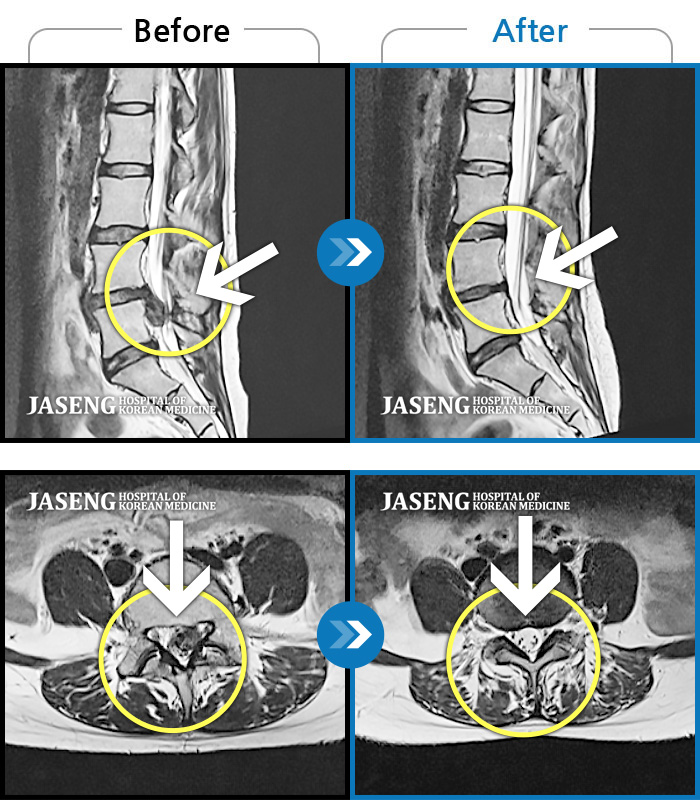

MRI 치료사례

왼쪽 꼬리뼈, 엉덩이, 다리 통증